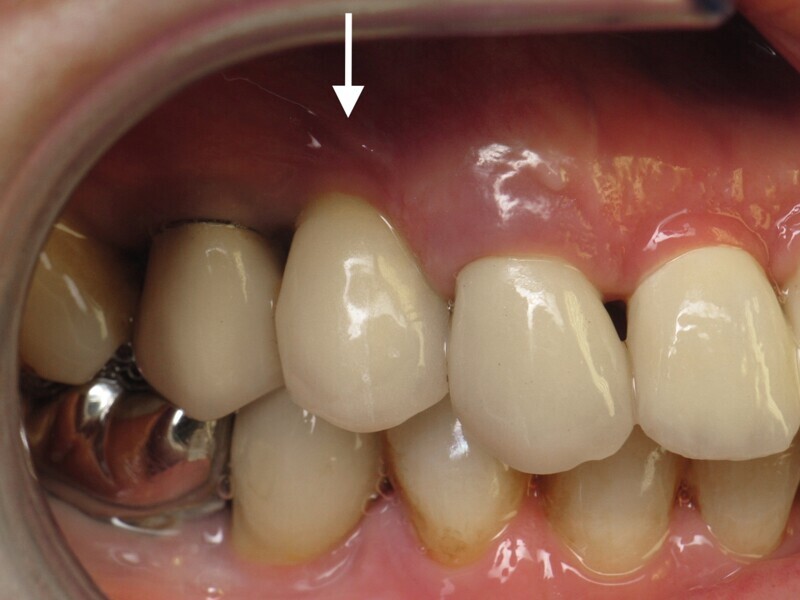

Il ne faut surtout pas être piégé par la hauteur d’os perdu et enfouir plus l’implant. Un tissue level est parfaitement stabilisé grâce à ses dernières spires. (Implant TL Straumann SP 4,1 RN, longueur 12 mm SLActive). Une incision limitée en étendue et en forme de « H » est réalisée dans le secteur de la dent de sagesse inférieure, pour un abord crestal. Un trépan de diamètre supérieur au trépan de calibrage (Fig. 5), donc 6 mm dans ce cas, permet de prélever une carotte de 4 mm de profondeur (Fig. 6). Elle forme un bloc circulaire cortico-spongieux qui est impactée en force, transversalement à l’implant (Fig. 7). La surface SLActive de l’implant est au contact de l’os spongieux richement vascularisée et la partie corticale protège cet ensemble et referme parfaitement le défaut osseux (Fig. 8). L’os greffé est entouré par l’os du site receveur sur tout le pourtour. Son immobilité totale permettra sa consolidation et sa revascularisation.4 Il n’est pas utile d’enfouir l’implant ni d’utiliser une membrane, car il n’y a pas de substitut osseux (Fig. 9). La couronne définitive est réalisée à trois mois (Fig. 10). Le suivi de cette patiente montre un excellent comportement ostéo-gingival à dix ans, tant radiologiquement (Fig. 11), que cliniquement (Fig. 12).

Une dent provisoire transvissée est confectionnée sur un pilier PMMA par couches successives de composite (Fig. 30). La couronne définitive céramo-zircone sur pilier variobase est transvissée à quatre mois. Un contrôle à deux ans montre une stabilité de l’environnement parodontal (Fig. 31).